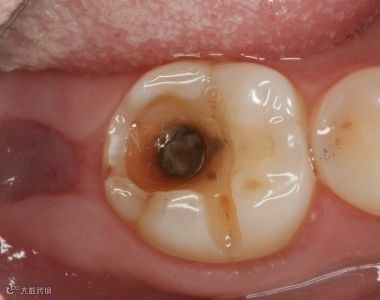

第二阶段:牙齿出现小黑洞,说明引起中度蛀牙,细菌腐蚀来到牙本质,伴随着牙齿敏感,黑色腐败物质其实就是细菌的产物,这时候还可以再补牙;

第三阶段:牙齿超过一半烂掉,说明已经重度蛀牙,细菌伤及牙髓牙神经,还伴随着剧烈疼痛,牙神经病变这时得根管治疗处理,挽救伤痕累累的牙齿。